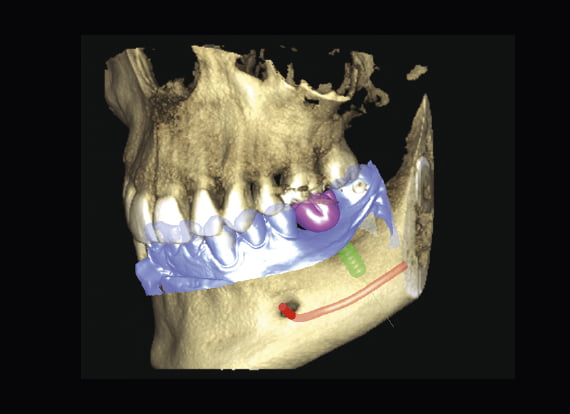

Tworzenie wirtualnych pacjentów

Jest to pierwszy system w branży, który łączy trzy różne typy danych 3D: skan CBCT, skan 3D twarzy i skan 3D modelu na jednym systemie rentgenowskim. To połączenie tworzy trójwymiarowego wirtualnego pacjenta w celu wizualizacji indywidualnych potrzeb klinicznych.